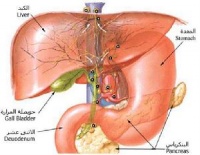

本症与精神因素关系密切,情绪波动或恐惧紧张时,可使症状加剧。副交感神经系统兴奋时也易发作。有些胃窦炎患者,上腹疼症状与十二指肠球部溃疡相似,慢性胃窦炎容易误诊为胃窦癌,需做胃镜检查来区别。

⑧患有慢性肝病、糖尿病、胆道疾病时,可使胃粘膜局部防御功能降低、胃功能紊乱而发生胃炎。另外扁桃体炎、鼻窦炎、龋齿感染等造成的带菌分泌物下咽,常可使胃粘膜屏障功能降低,诱发胃炎。